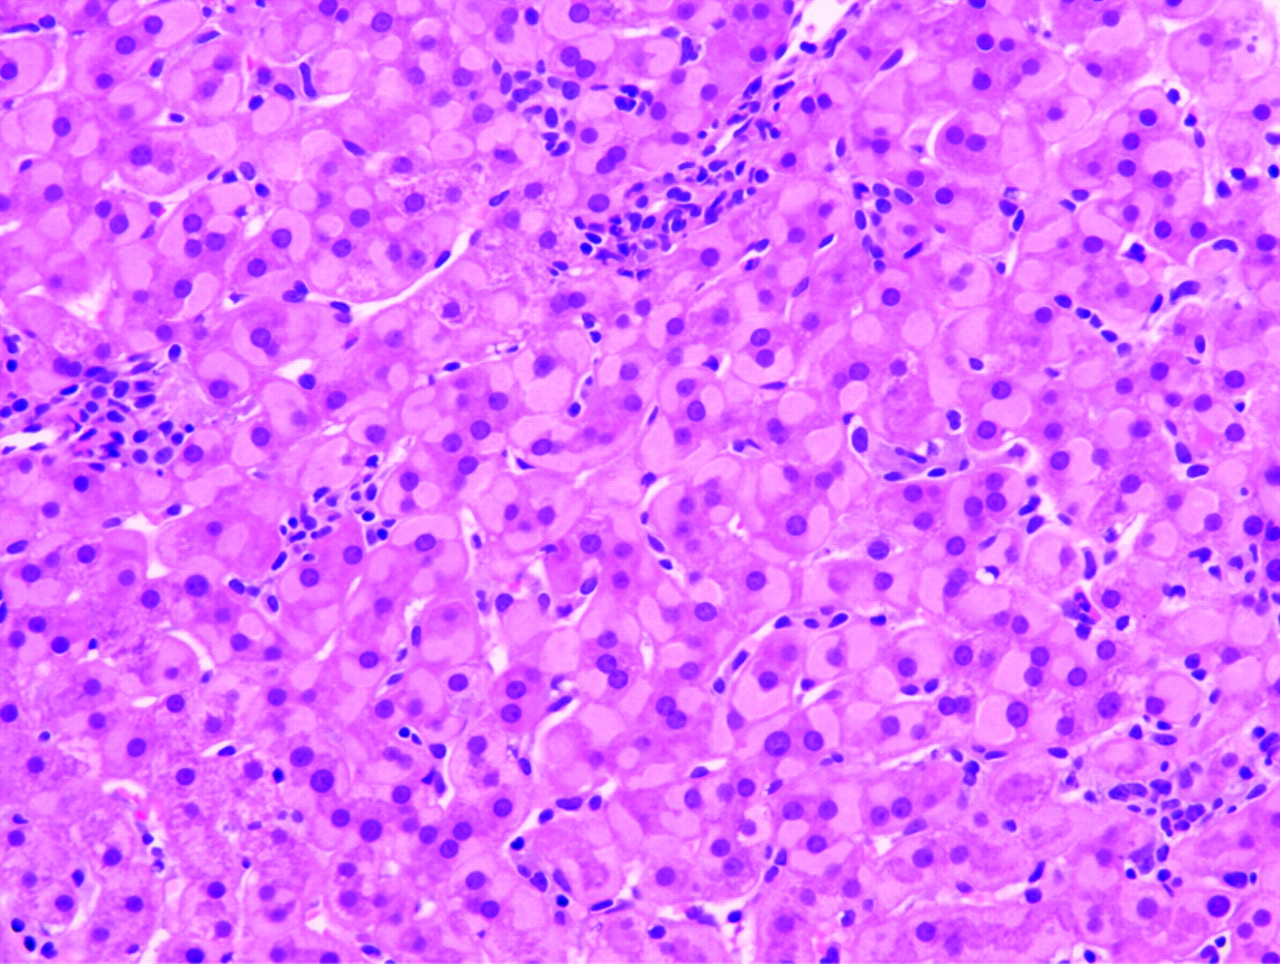

Patient with NPDB showing hepatosplenomegaly. Download Scientific Ground Glass Appearance Find out the difference between diffuse and focal ground glass, and the. It may or may not be cancer, depending. Ground glass opacity is a radiologist's term for a nodule that looks hazy on a scan. Learn about the types, causes, and symptoms of ggo,. Ggo is a ct scan finding that indicates abnormal density in the lungs, which can. Ground Glass Appearance.